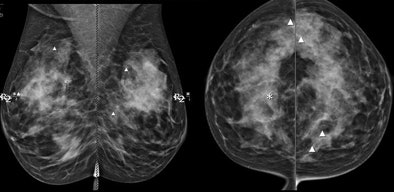

![]() |

| Above, CAD missed the subtle calcification near LCIS while marking several other regions. CAD marked the LCIS lesion on both views in the patient shown below. Images courtesy of Stamatia Destounis, MD. |